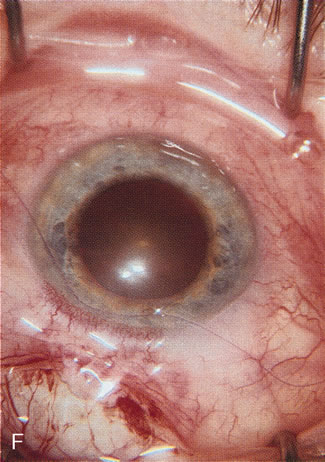

Fig. 1. The anatomic advantage of small incision cataract surgery for the glaucoma patient. A. Long-term bleb function with a large cataract incision is difficult to achieve with either ECCE-trabeculectomy or trabeculectomy followed later by ECCE. This bleb failed to form sufficiently when combined with large incision ECCE. The inflammation, bleeding, and long-term wound healing with stimulation of fibroblasts associated with this technique are more likely to cause bleb failure. In addition, the increased iris manipulation necessary to deliver the nucleus and subsequent iris repair adds to the long-term breakdown of the blood aqueous barrier. B and C. Two-site phacotrabeculectomy has the advantage of small incision cataract surgery combined with separate site trabeculectomy. The incision size is one third the size of the standard ECCE. The inflammation is less severe, and cataract wound healing is confined to the temporal area. Visual rehabilitation with phacoemulsification and foldable IOL is much faster. Phacoemulsification allows successful lens extraction even in the unfriendly environment of a smaller pupil compared with ECCE. The trabeculectomy is performed in an entirely different site, well away from the wound healing associated with temporal phacoemulsification. The likelihood of this filter functioning long-term is greater than with ECCE-trabeculectomy. D. The surgeon also has the option of single-site phacotrabeculectomy with foldable IOL. Both the lens extraction and trabeculectomy are performed through one small 3.5-mm limbal incision.

Fig. 2. Wound modulation and revision. A. MMC decreases the likelihood of bleb failure in high-risk eyes undergoing combined cataract and glaucoma surgery. Overusage of this potent cytotoxic drug should be avoided owing to a myriad of problems related to the formation of an avascular bleb. B. Office-based laser revision of the operative wound allows for increased postoperative flexibility with less complications. The correct number and tension of scleral flap sutures allows the surgeon to strive for a safe immediate postoperative IOP range. When fibrosis occurs at approximately 1 week, suturelysis or release of sutures increases filtration while avoiding unwanted hypotony.